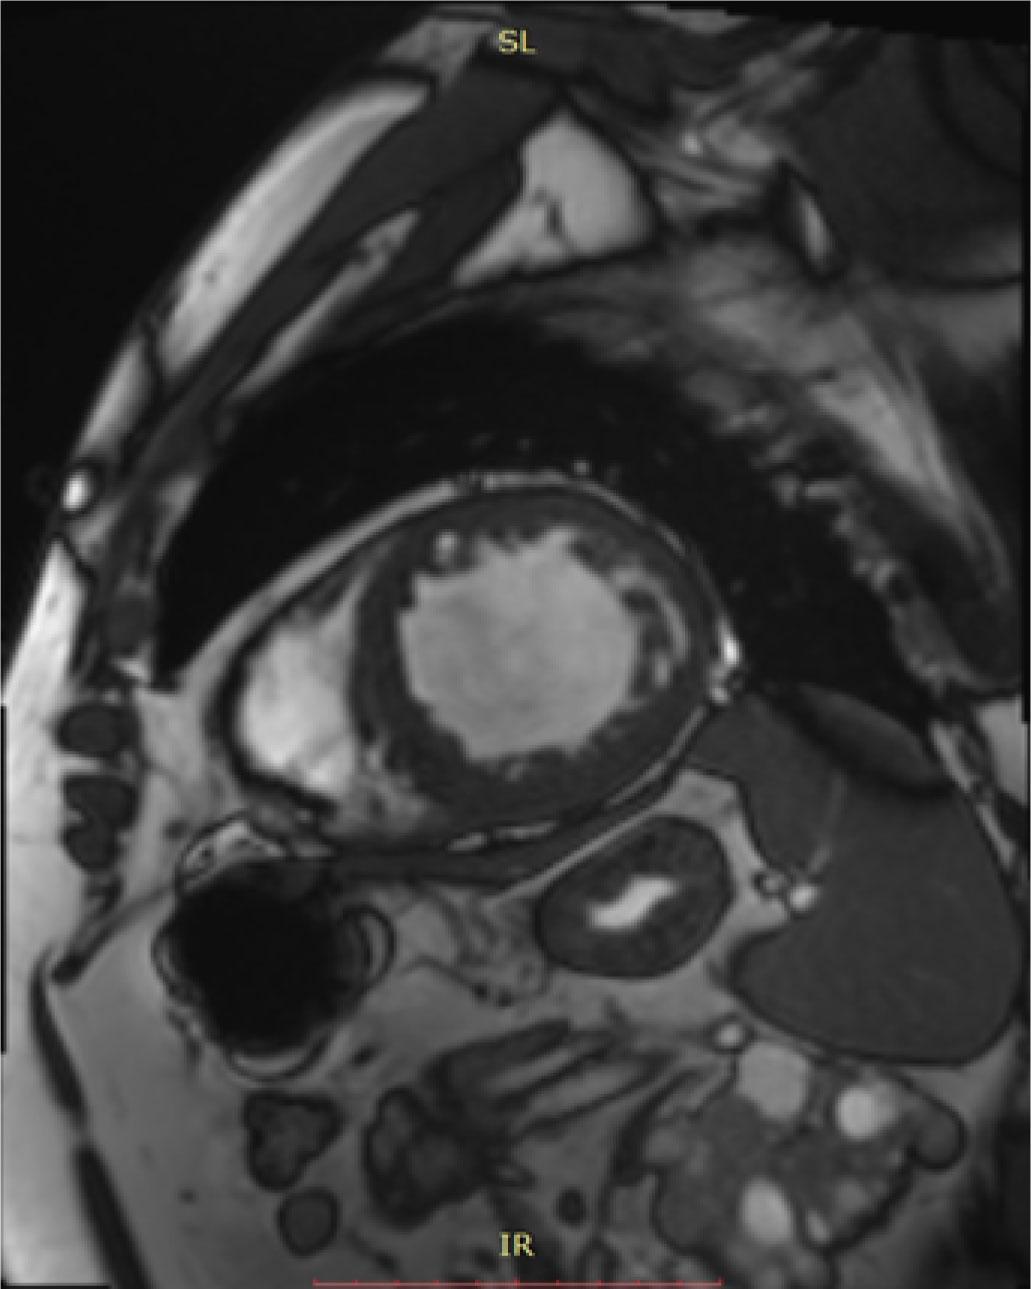

We performed further tests to assess the etiology of the LV systolic function impairment. Coronary angiography did not show significant lesions of the epicardial coronary arteries. Cardiac MRI (Figure 2) showed LV with increased indexed volumes (end-diastolic volume 108.54 ml/m2, end-systolic volume 68.34 ml/m2), with reduced systolic function (ejection fraction 37%, moderate global hypokinesia with severe hypokinesia - akinesia of the lower segment from the basal level to the middle cavity level), as well as increased mass index (136 g/m2). Additionally, the MRI revealed the maximum thickness of the LV myocardium to be 13 mm basal antero-septal and evident trabeculations at the level of the LV myocardium from the level of the middle cavity to the apex, associated with a fragmented appearance of the papillary muscles, fulfilling the criterion of non-compaction at the level of 6 segments (maximum noncompacted to compacted end-diastolic ratio 2.67), right ventricle with normal volumes and systolic function at the lower limit of normal – right ventricle ejection fraction 47%, mild-moderate mitral insufficiency. No areas of myocardial edema, scar areas or LV myocardial fibrosis, intracardiac thrombosis, or microvascular obstruction were apparent. Therefore, we concluded that the patient had heart failure due to non-compaction cardiomyopathy.

Cardiac magnetic resonance imaging showing left ventricular non-compaction criteria